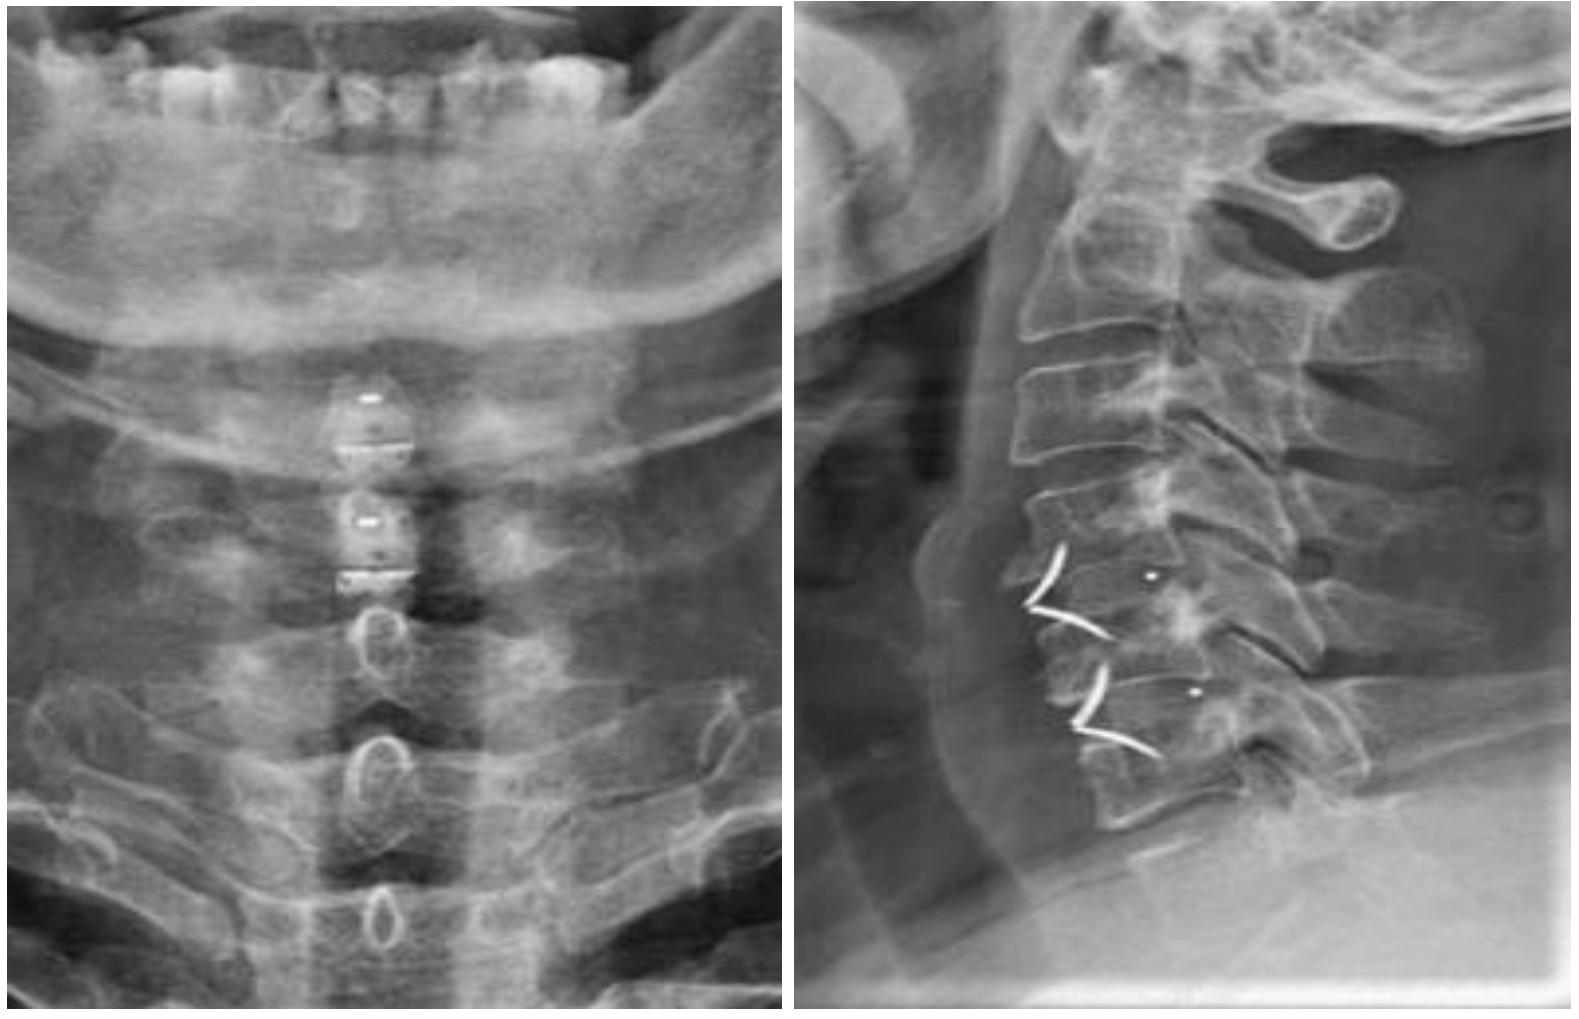

颈椎外伤后行:颈椎前路椎管减压、椎间盘切除、椎体次全切除、钛笼植入椎间融合、钢板螺钉内固定术及颈椎后路椎板切除减压、侧块螺钉内固定术